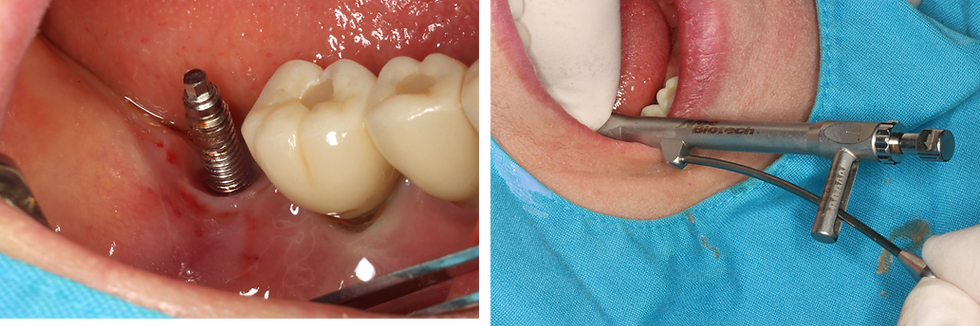

2️⃣ Fixture remove

Assembly of the remover hex and remover positioner from the All-in-One Remover Kit prior to fixture removal.

After connecting the remover system to the #47 fixture, a torque of 60 Ncm was applied to ensure stable engagement for fixture removal.

Although an R/W driver is generally indicated, a one-size smaller driver was selected based on intraoperative assessment to achieve more stable engagement

The fixture driver was tightened in a counterclockwise direction, and a torque of 200 N·cm was applied to remove the fixture.